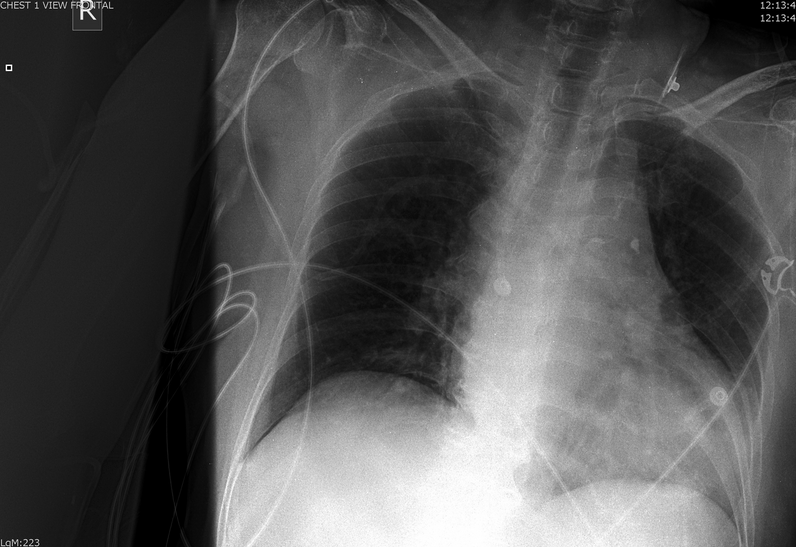

In a recent article in the Journal of Emergency Medicine, Dr. Resa Lewiss and friends, discuss 2 cases of thoracic aortic aneurysm identification by focused cardiac ultrasound. It is a great case report that highlights the need to include the aortic root and descending thoracic aorta in the parasternal long view of your focused cardiac echo.

“A 60-year-old man presented to the emergency department (ED) after a blunt traumatic injury to his back while at work. During the focused cardiac ultrasound examination, the aortic outflow tract distal to the aortic valve appeared enlarged and the aortic root measured 5.49 cm.

Screen Shot 2014-03-04 at 9.16.55 AM